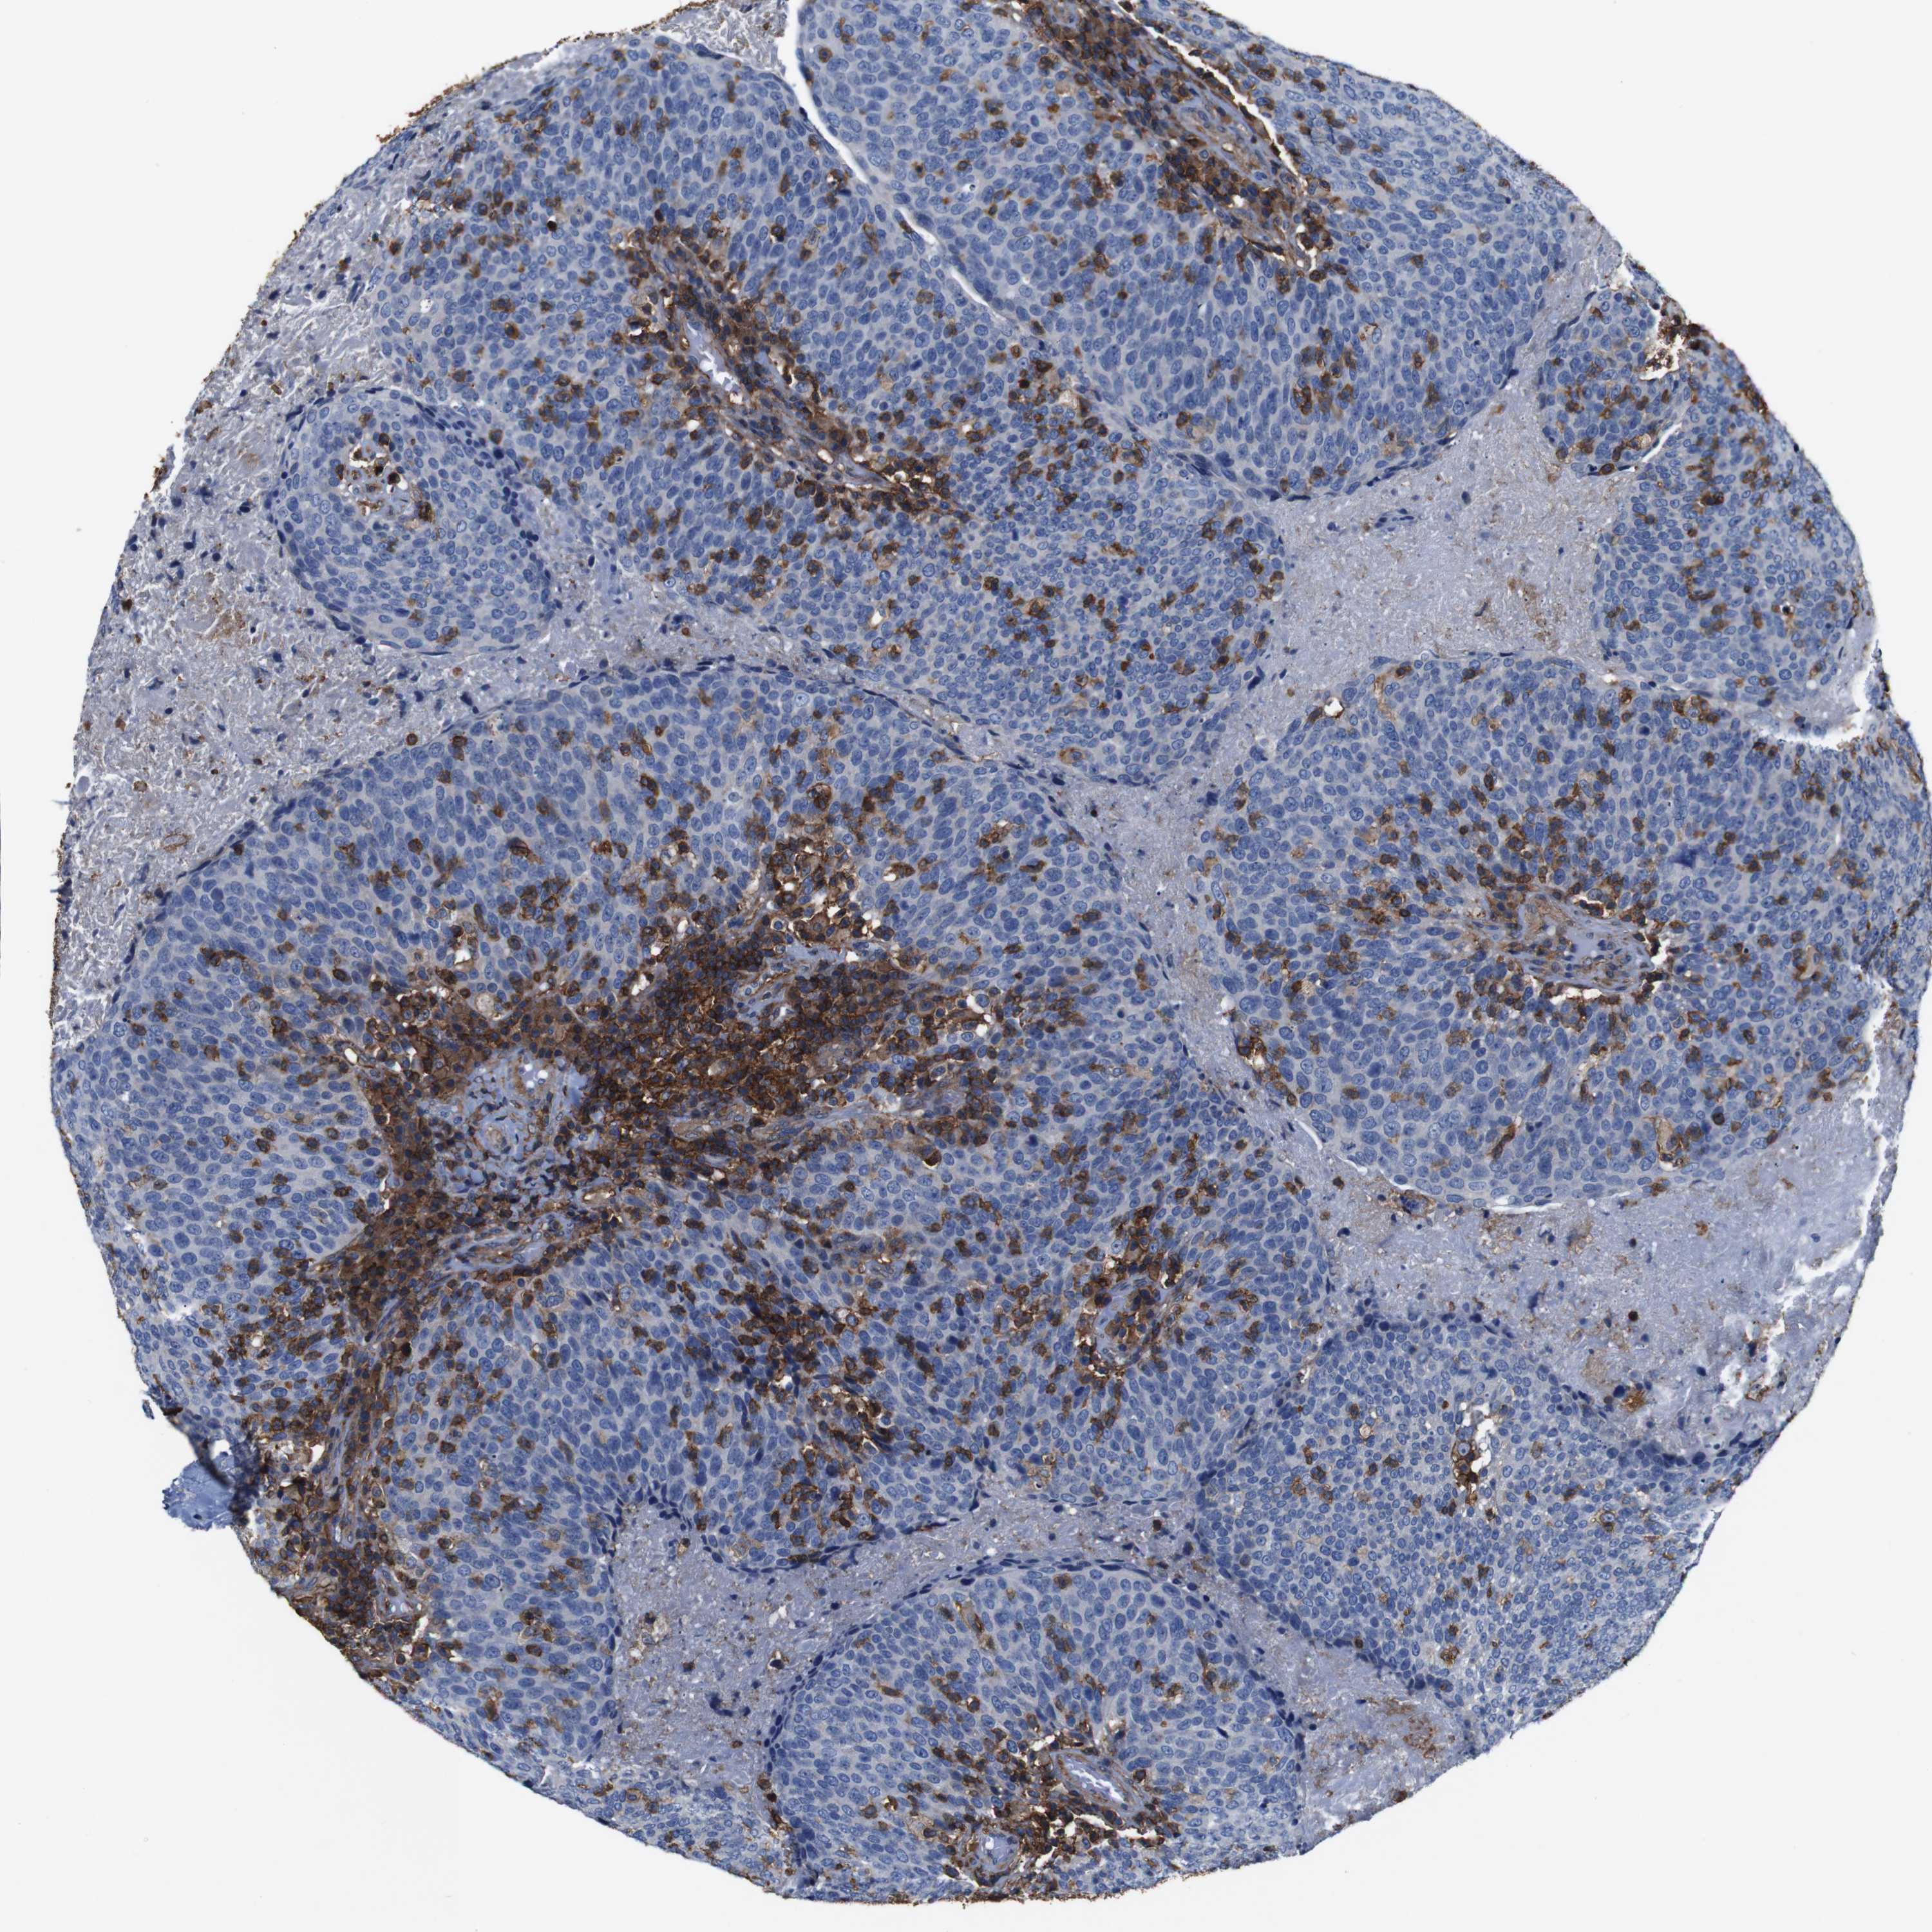

HEAD AND NECK CANCER - Protein expressioni

A mouse-over function shows sample information and annotation data. Click on an image to view it in a full screen mode. Samples can be filtered based on level of antibody staining by selecting one or several of the following categories: high, medium, low and not detected. The assay and annotation is described here.

Antibody stainingi

Antibody staining in the annotated cell types in the current human tissue is reported as not detected, low, medium, or high, based on conventional immunohistochemistry profiling in selected tissues. This score is based on the combination of the staining intensity and fraction of stained cells.

Each image is clickable and will lead to virtual microscopy that enables deeper exploration of all samples and also displays staining intensity scores, fraction scores and subcellular localization as well as patient and tissue information for each sample.

Antibody CAB009092

Staining

High

Medium

Low

Not detected

Intensity

Strong

Moderate

Weak

Negative

Quantity

>75%

75%-25%

<25%

None

Location

Nuclear

Cytoplasmic/membranous

Cytoplasmic/membranous,nuclear

Squamous cell carcinoma, NOS

Squamous cell carcinoma, metastatic, NOS

Adenocarcinoma, NOS